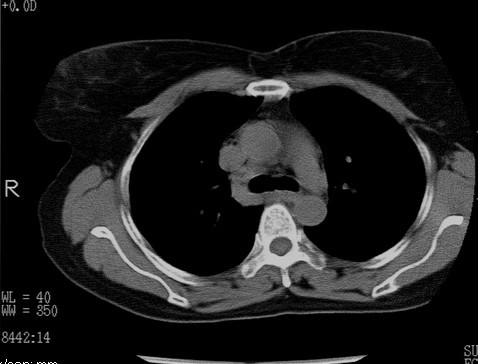

以下是引用随光逐影在2010-3-1 8:36:00的发言:[br]右上纵隔囊性占位性病变,考虑支气管囊肿,不排除神经源性肿瘤。